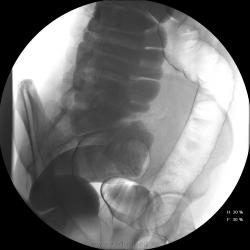

Девушка, 27 лет, жалуется на периодические боли в правой подвздошной области, области паха справа. Во время этого идет нарушение стула - то слабит, то несколько дней не может ходить в туалет, вздутие кишечника. Жалобы несколько лет . Обследованна кем только можно. Хирург посоветовал ирригоскопию. Работа достаточно нервная. До первого случая данных проблем , за неделю, проходила сан лечение в пансионате ( для поднятия общего иммунитета - так говорит), был курс клизм с травами - сама думает, что это не связанно.

Цепочка тенюшек - это наша "гордость)" следы от контраста после гистеросальпингоскопии. чтоб вымыть ,надо разбирать стол , а это только с представителем сименса. вот так.) а правые отделы толстой кишки на расширены? я кроме лополнительной петли сигмы сам ничего не вижу. несколько настораживает некоторое расширение правых отделов кишки- может за счет запоров, которые случаются у девушки? не хочется что то пропустить.

Коллеги, значит пишу долихосигма и все?

Считаю, данных за долихосигму нет.

А образованый петлями ее клубок - вариант нормы? не может ли он давать запоры?

Признак долихосигмы - это наличие т.н. симптома "трехстволки", есть это - есть и долихосигма. В данном случае такой вариант имеет место быть.